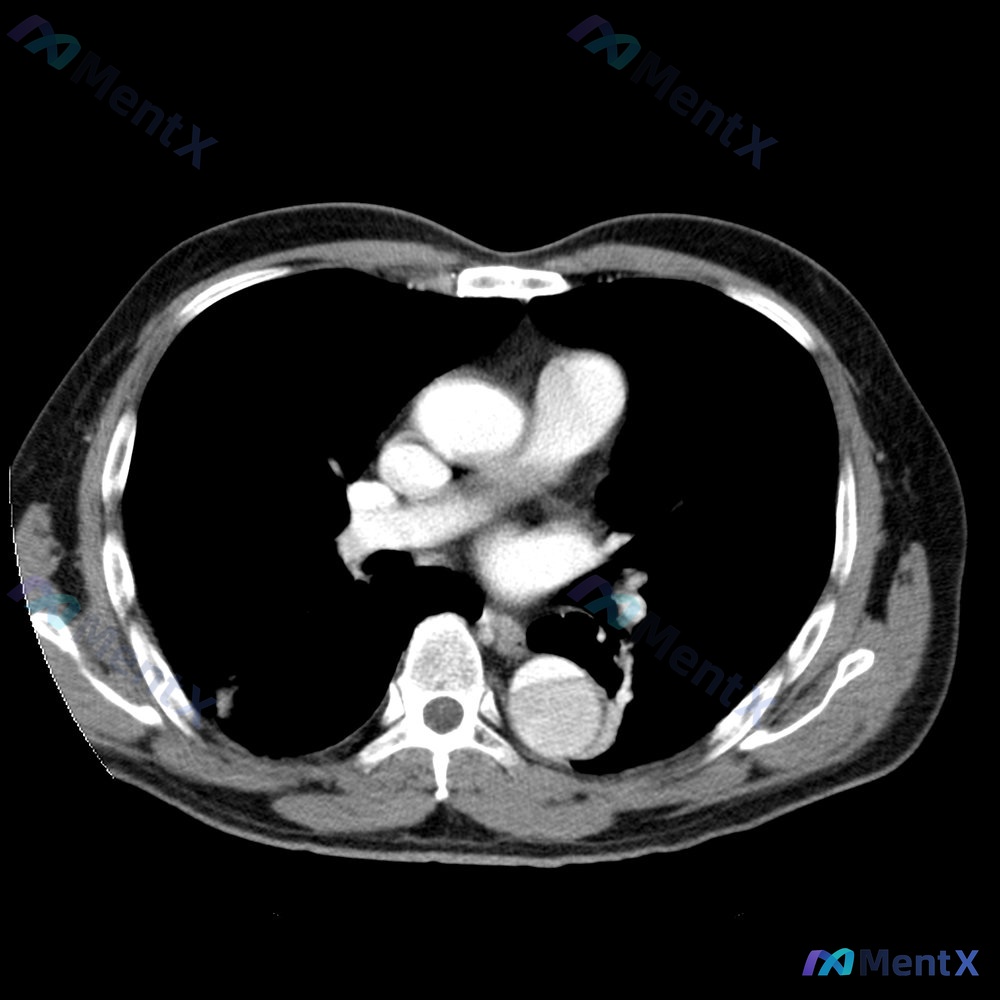

整理了一个挺有警示意义的急性胸痛病例,从症状到影像再到决策,每一步都可能踩坑,分享一下我的分析思路: --- 病例核心信息 患者:48岁男性 主诉:突发胸痛、气促1小时 关键病史:高血压(氢氯噻嗪+赖诺普利)、30年包天吸烟史 疼痛特点:剧烈、撕裂样,向背部放射 生命体征:HR 105bpm,RR...